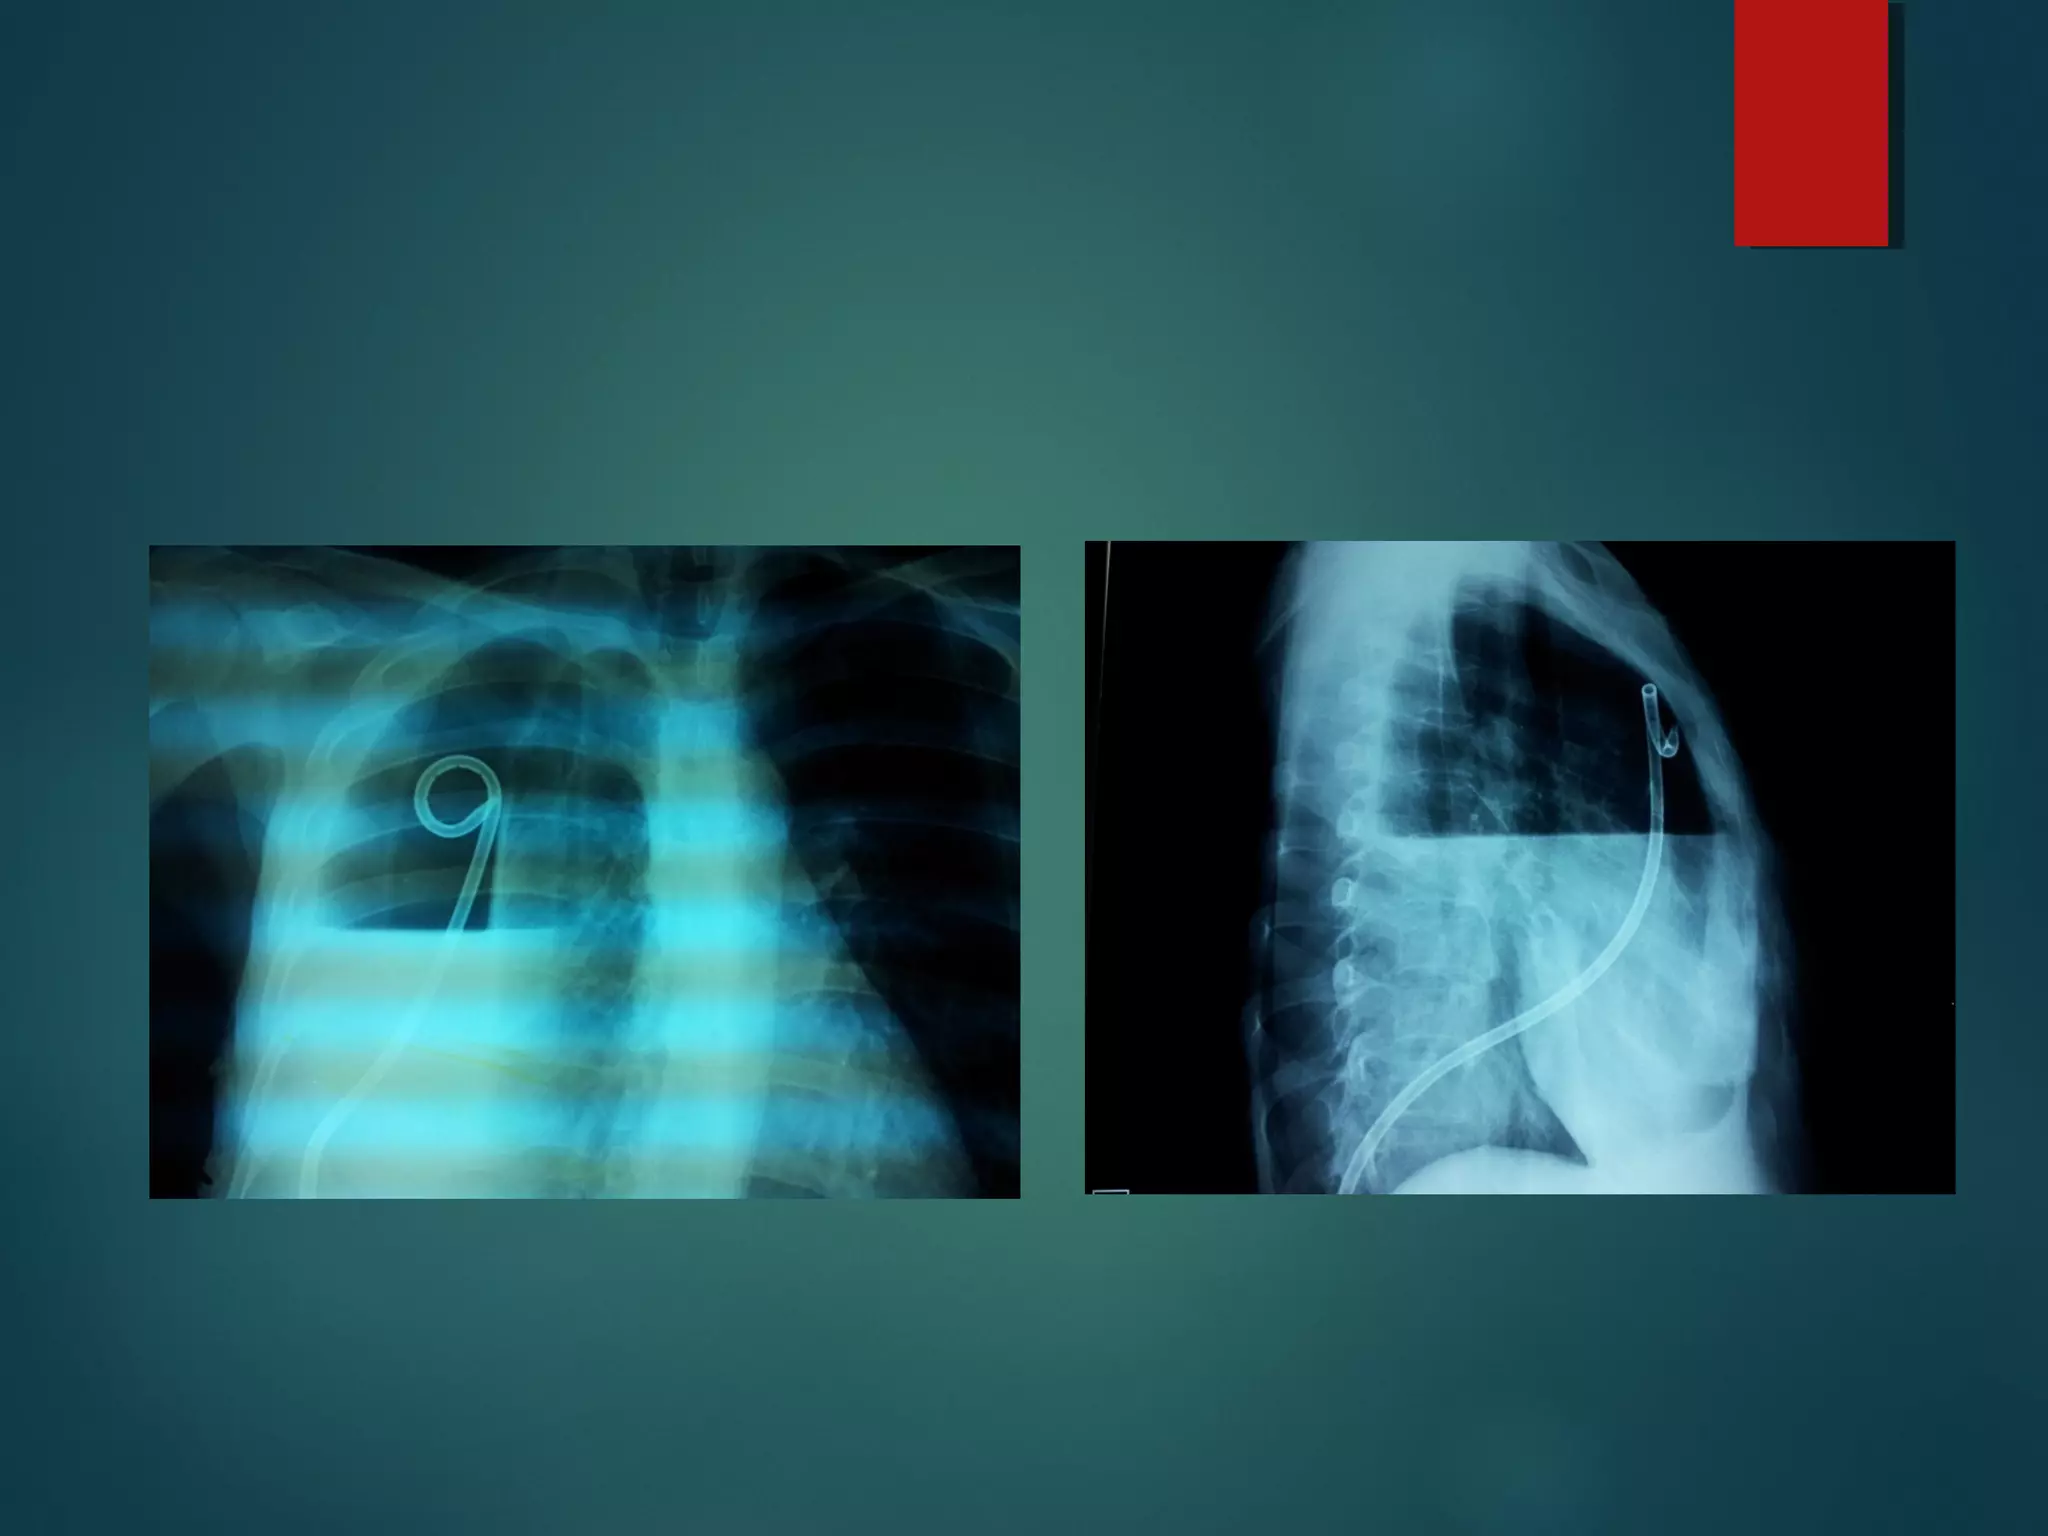

Lateral cxr

 opacity convex anteriorly.

Tapering at its upper and

lower ends

Extending into the thorax.

D – shaped shadow.